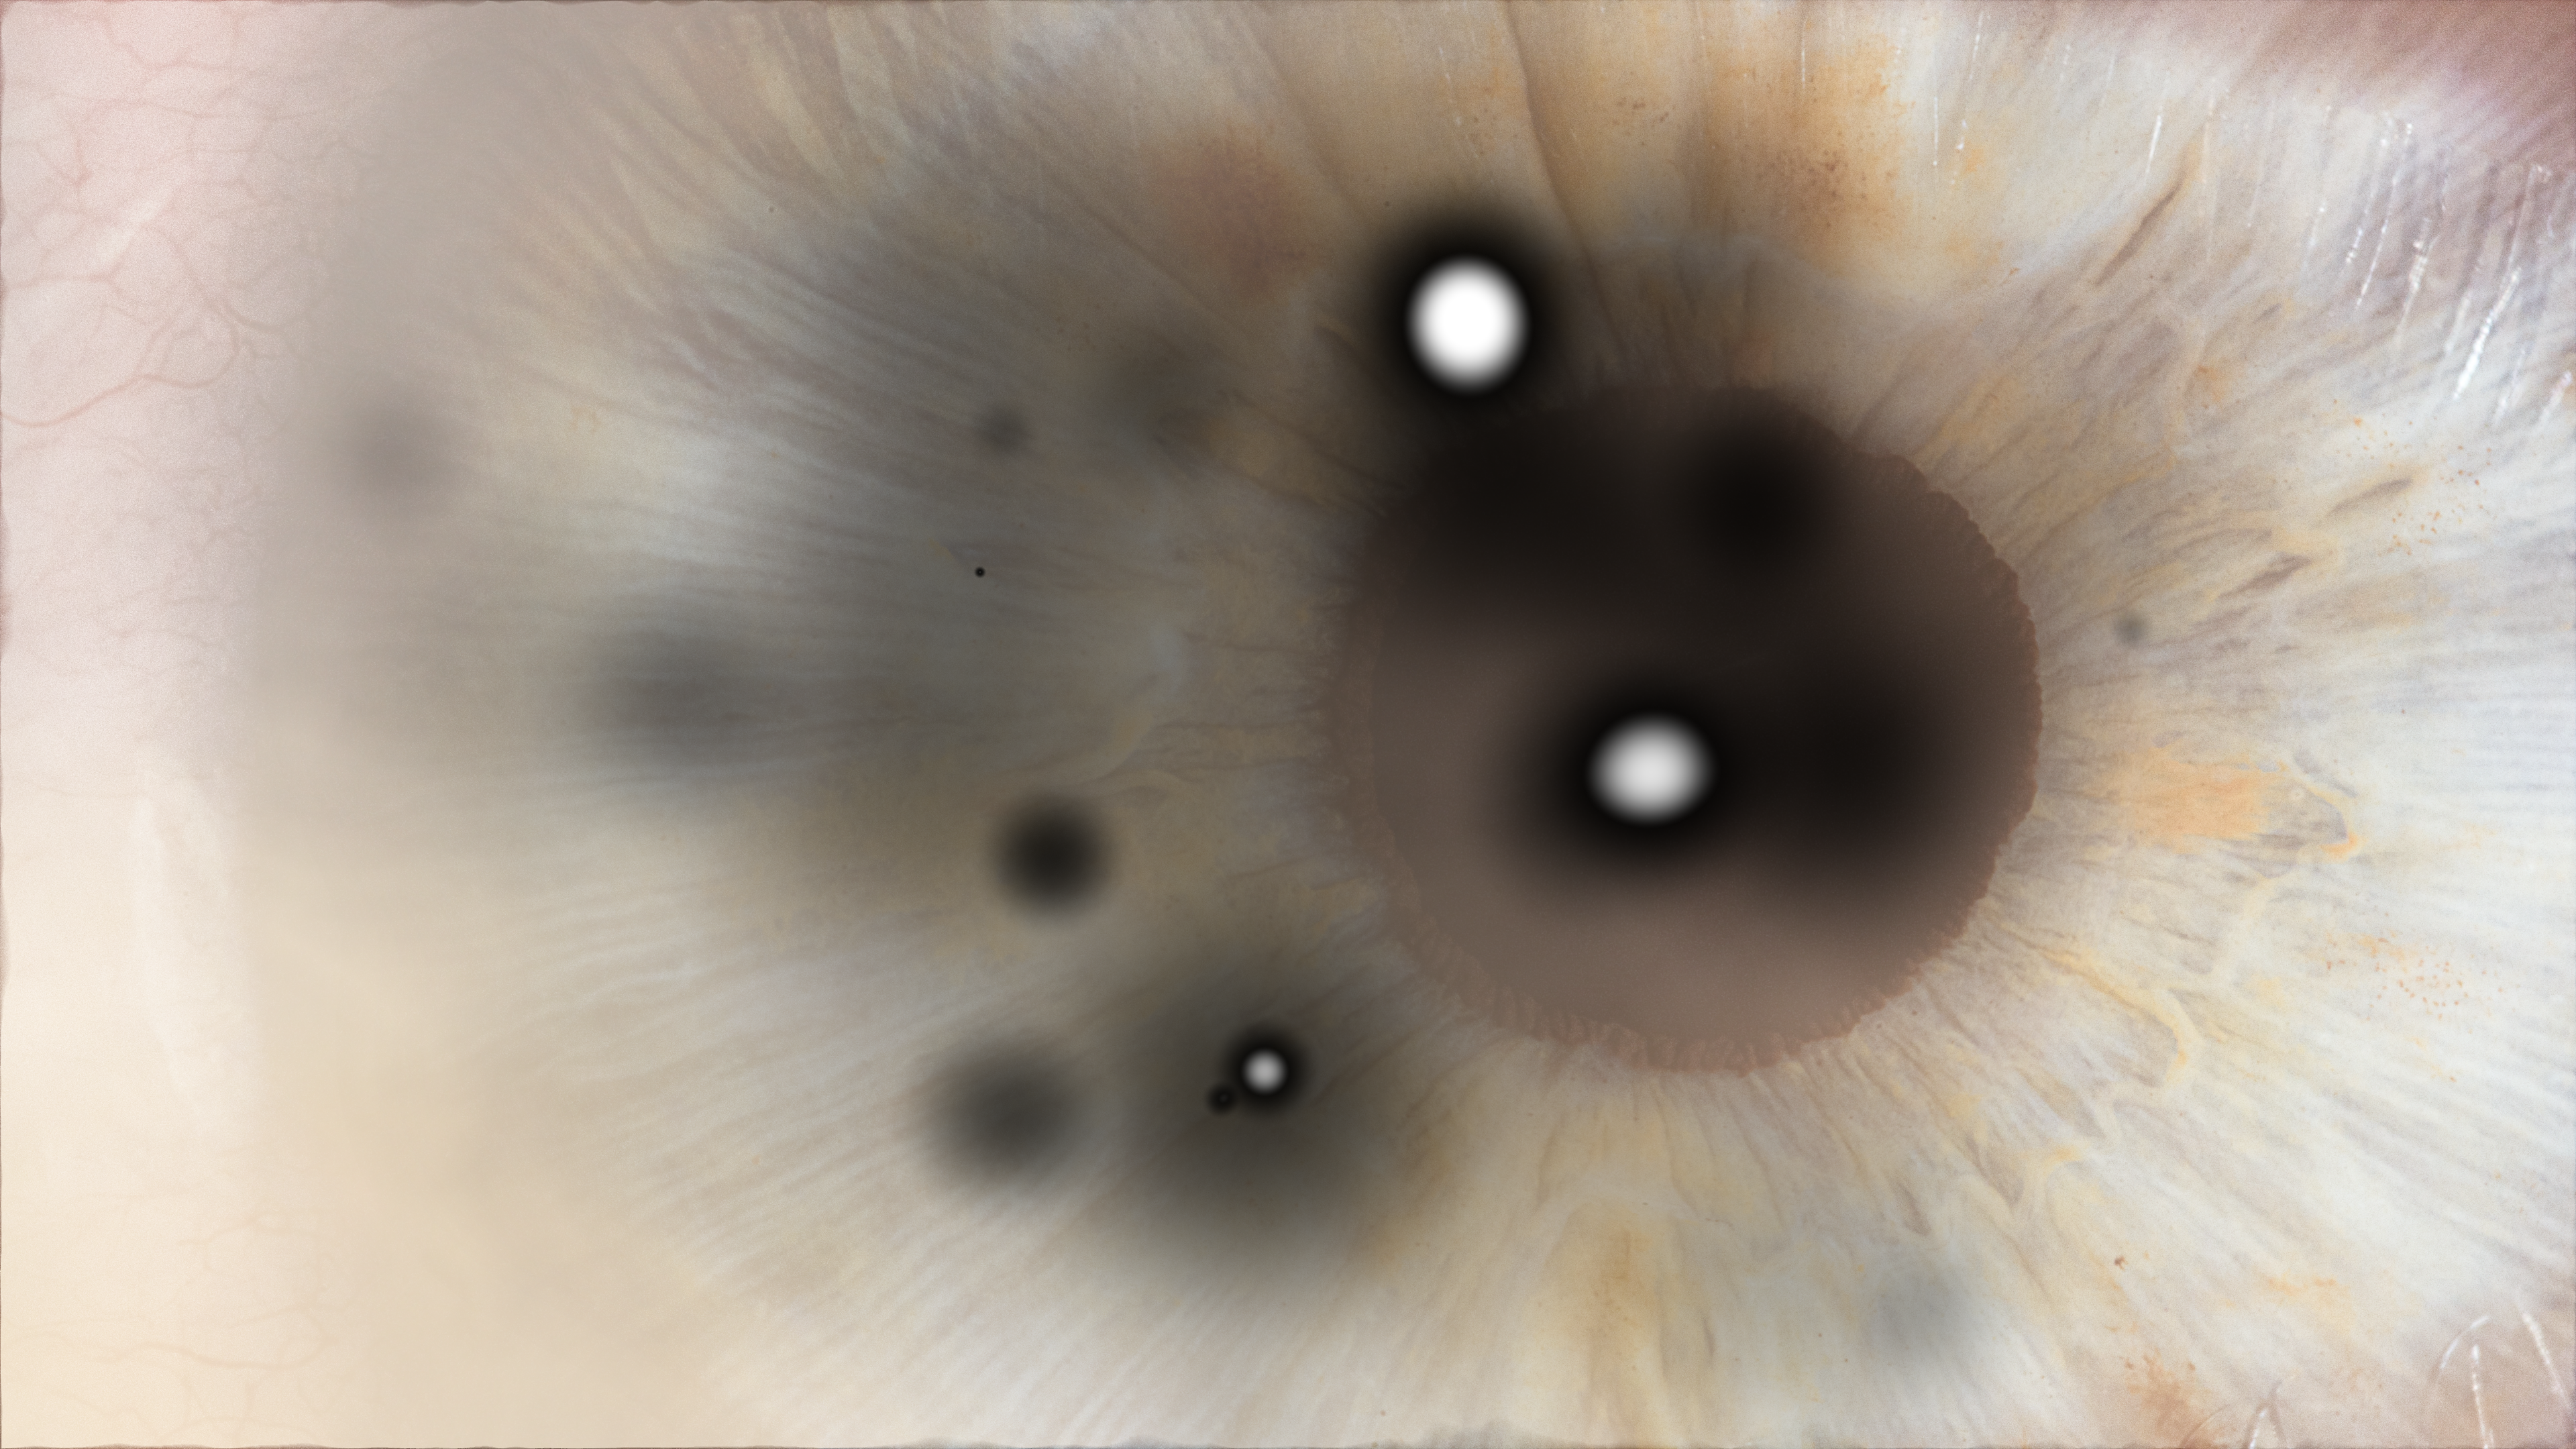

By breaking the darkness inside his eyes, He, the tortured soul, tried to imagine the world without having seen it. Walking slowly in his red coat, he’s smelling the flowers in the valley, touching the sky with his head. He’s in front of me, above the river… He’s flying!